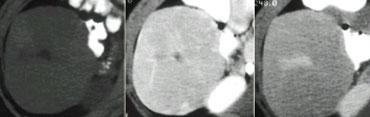

Bốn loại u khác nhau ngấm thuốc trong thì động mạch muộn. Từ trái sang phải: HCC trên nền gan xơ; FNH có sẹo trung tâm ở bệnh nhân trẻ; u tuyến ở phụ nữ trẻ dùng thuốc tránh thai và cuối cùng là u máu với đặc điểm ngấm thuốc điển hình ở các thì khác (không hiển thị).

Các tổn thương tăng sinh mạch có thể trông rất giống nhau trong thì động mạch (hình).

Việc phân biệt được thực hiện bằng cách đánh giá đặc điểm ngấm thuốc ở các thì khác và các đặc điểm đại thể bệnh lý bổ sung kết hợp với dữ liệu lâm sàng.

Di căn tăng sinh mạch được xem xét ở bệnh nhân có u nguyên phát đã biết.

Nhìn chung, HCC được nghĩ đến khi có bối cảnh xơ gan, trong khi FNH được xem xét ở phụ nữ trẻ và u tuyến gan ở bệnh nhân dùng thuốc tránh thai đường uống, steroid đồng hóa hoặc có tiền sử bệnh dự trữ glycogen.

Tổn thương giảm sinh mạch

U gan giảm sinh mạch phổ biến hơn u tăng sinh mạch.

Hầu hết các tổn thương giảm sinh mạch đều ác tính và di căn là loại phổ biến nhất.

Mặc dù u gan nguyên phát thường tăng sinh mạch, vẫn có ngoại lệ. 10% HCC là giảm sinh mạch. Ung thư biểu mô đường mật (cholangiocarcinoma) giảm sinh mạch nhưng có thể ngấm thuốc muộn (hình).

Bên trái là một khối giảm sinh mạch với ngấm thuốc không đều trong thì động mạch muộn và thì tĩnh mạch cửa muộn. Đây là dấu hiệu của ác tính.

Trên các hình ảnh thì muộn, quan sát thấy một cấu trúc tương đối tăng tỷ trọng ở trung tâm, thải thuốc chậm hơn so với nhu mô gan bình thường.

Điều này cho thấy khối u này chủ yếu được cấu thành bởi mô xơ.

Mô xơ cũng gây co rút bao gan.

Các đặc điểm hình ảnh này rất gợi ý chẩn đoán ung thư biểu mô đường mật.